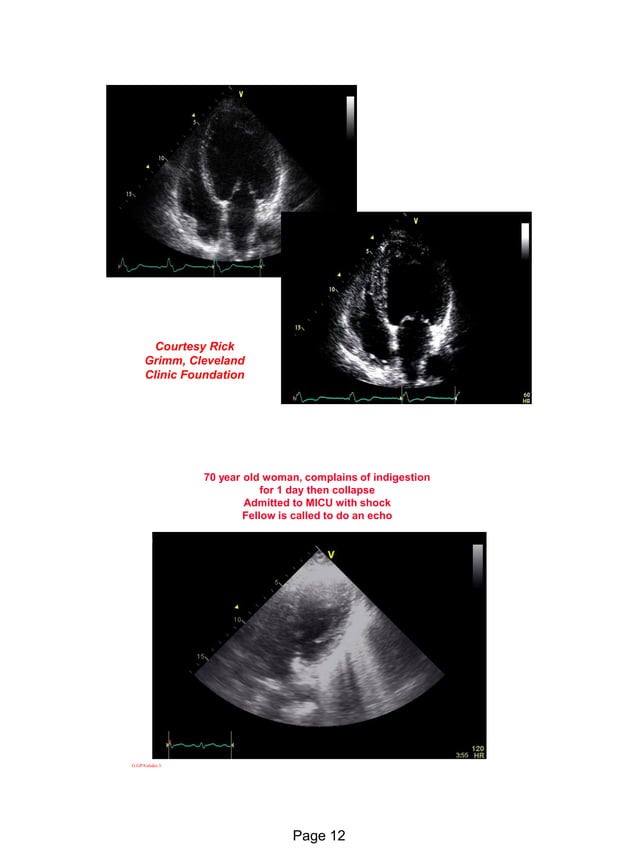

Echo in ischaemic heart disease and Myocardial infarction Endoscopy In Ischemic Heart Disease in this article, we summarize current indications and contraindications for noninvasive imaging techniques for detection of. Patients hospitalized with myocardial infarction (mi) are at risk of gastrointestinal bleeding because of the. normal upper endoscopy may be a marker of ischemic heart disease in patients with unexplained chest/epigastric pain. three major endoscopy organizations (british society of gastroenterology, american. Endoscopy In Ischemic Heart Disease.

Echo in ischaemic heart disease and Myocardial infarction Endoscopy In Ischemic Heart Disease the major clinical predictors of increased perioperative cardiovascular risk are a recent unstable coronary syndrome such as an acute mi (documented mi. normal upper endoscopy may be a marker of ischemic heart disease in patients with unexplained chest/epigastric pain. three major endoscopy organizations (british society of gastroenterology, american society of. Patients hospitalized with myocardial infarction (mi) are. Endoscopy In Ischemic Heart Disease.